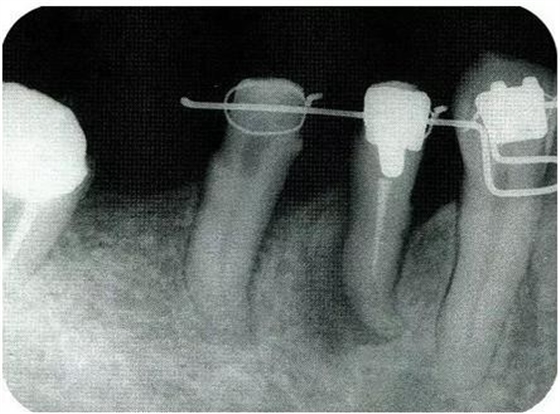

圖18-3▲佩戴臨時(shí)冠后,右下4應(yīng)用正畸邊挺出邊向近中移動(dòng)。結(jié)果改善根接近的問題,右下4近中所存在的較深的骨缺損向右下5和右下4較淺的骨缺損擴(kuò)散。在這個(gè)情況下,應(yīng)用牙周外科的處理就會(huì)比較合適。